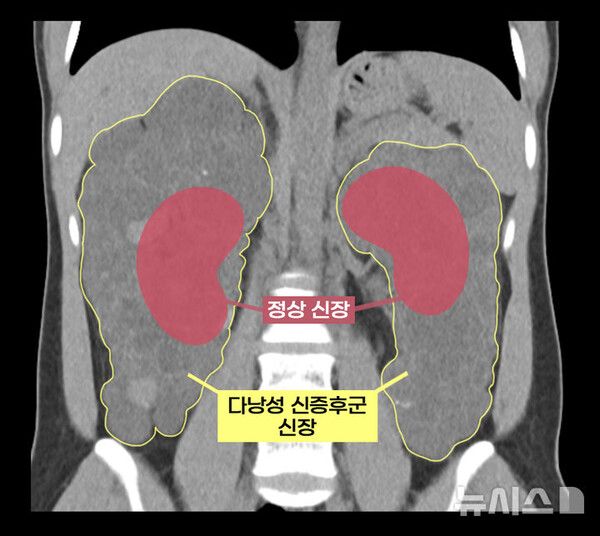

국내 의료진이 다낭성 신증후군으로 신장이 7배나 커진 환자를 대상으로 로봇을 이용해 비대해진 신장을 안전하게 제거하고 공여자의 건강한 신장을 이식하는 데 성공했다. 다낭성 신증후군 환자에게 로봇 신장이식을 성공한 것은 아시아 최초이자 전 세계 세 번째다.

이 씨는 상염색체 우성 다낭성 신증후군을 앓았다. 다낭성 신증후군은 신장에 셀 수없이 많은 낭종이 발생해 신장이 최대 축구공만큼 커지는 유전 질환이다. 1,000명 중 한 명꼴로 비교적 흔하게 발생하며 대부분 만성 신부전으로 이어진다.

보통의 만성 신부전 환자는 신장이식을 할 때 기존 신장을 그대로 두지만, 다낭성 신증후군 환자는 기존 신장을 떼어내야 한다. 이미 신장이 비대해진 상태이므로 새로운 신장이 들어올 공간을 확보해야 할 뿐만 아니라 낭종 감염과 낭종 파열로 인한 출혈, 신장암 발병 등의 합병증 위험이 있어 양측 신장을 제거하고 신장이식을 진행한다.